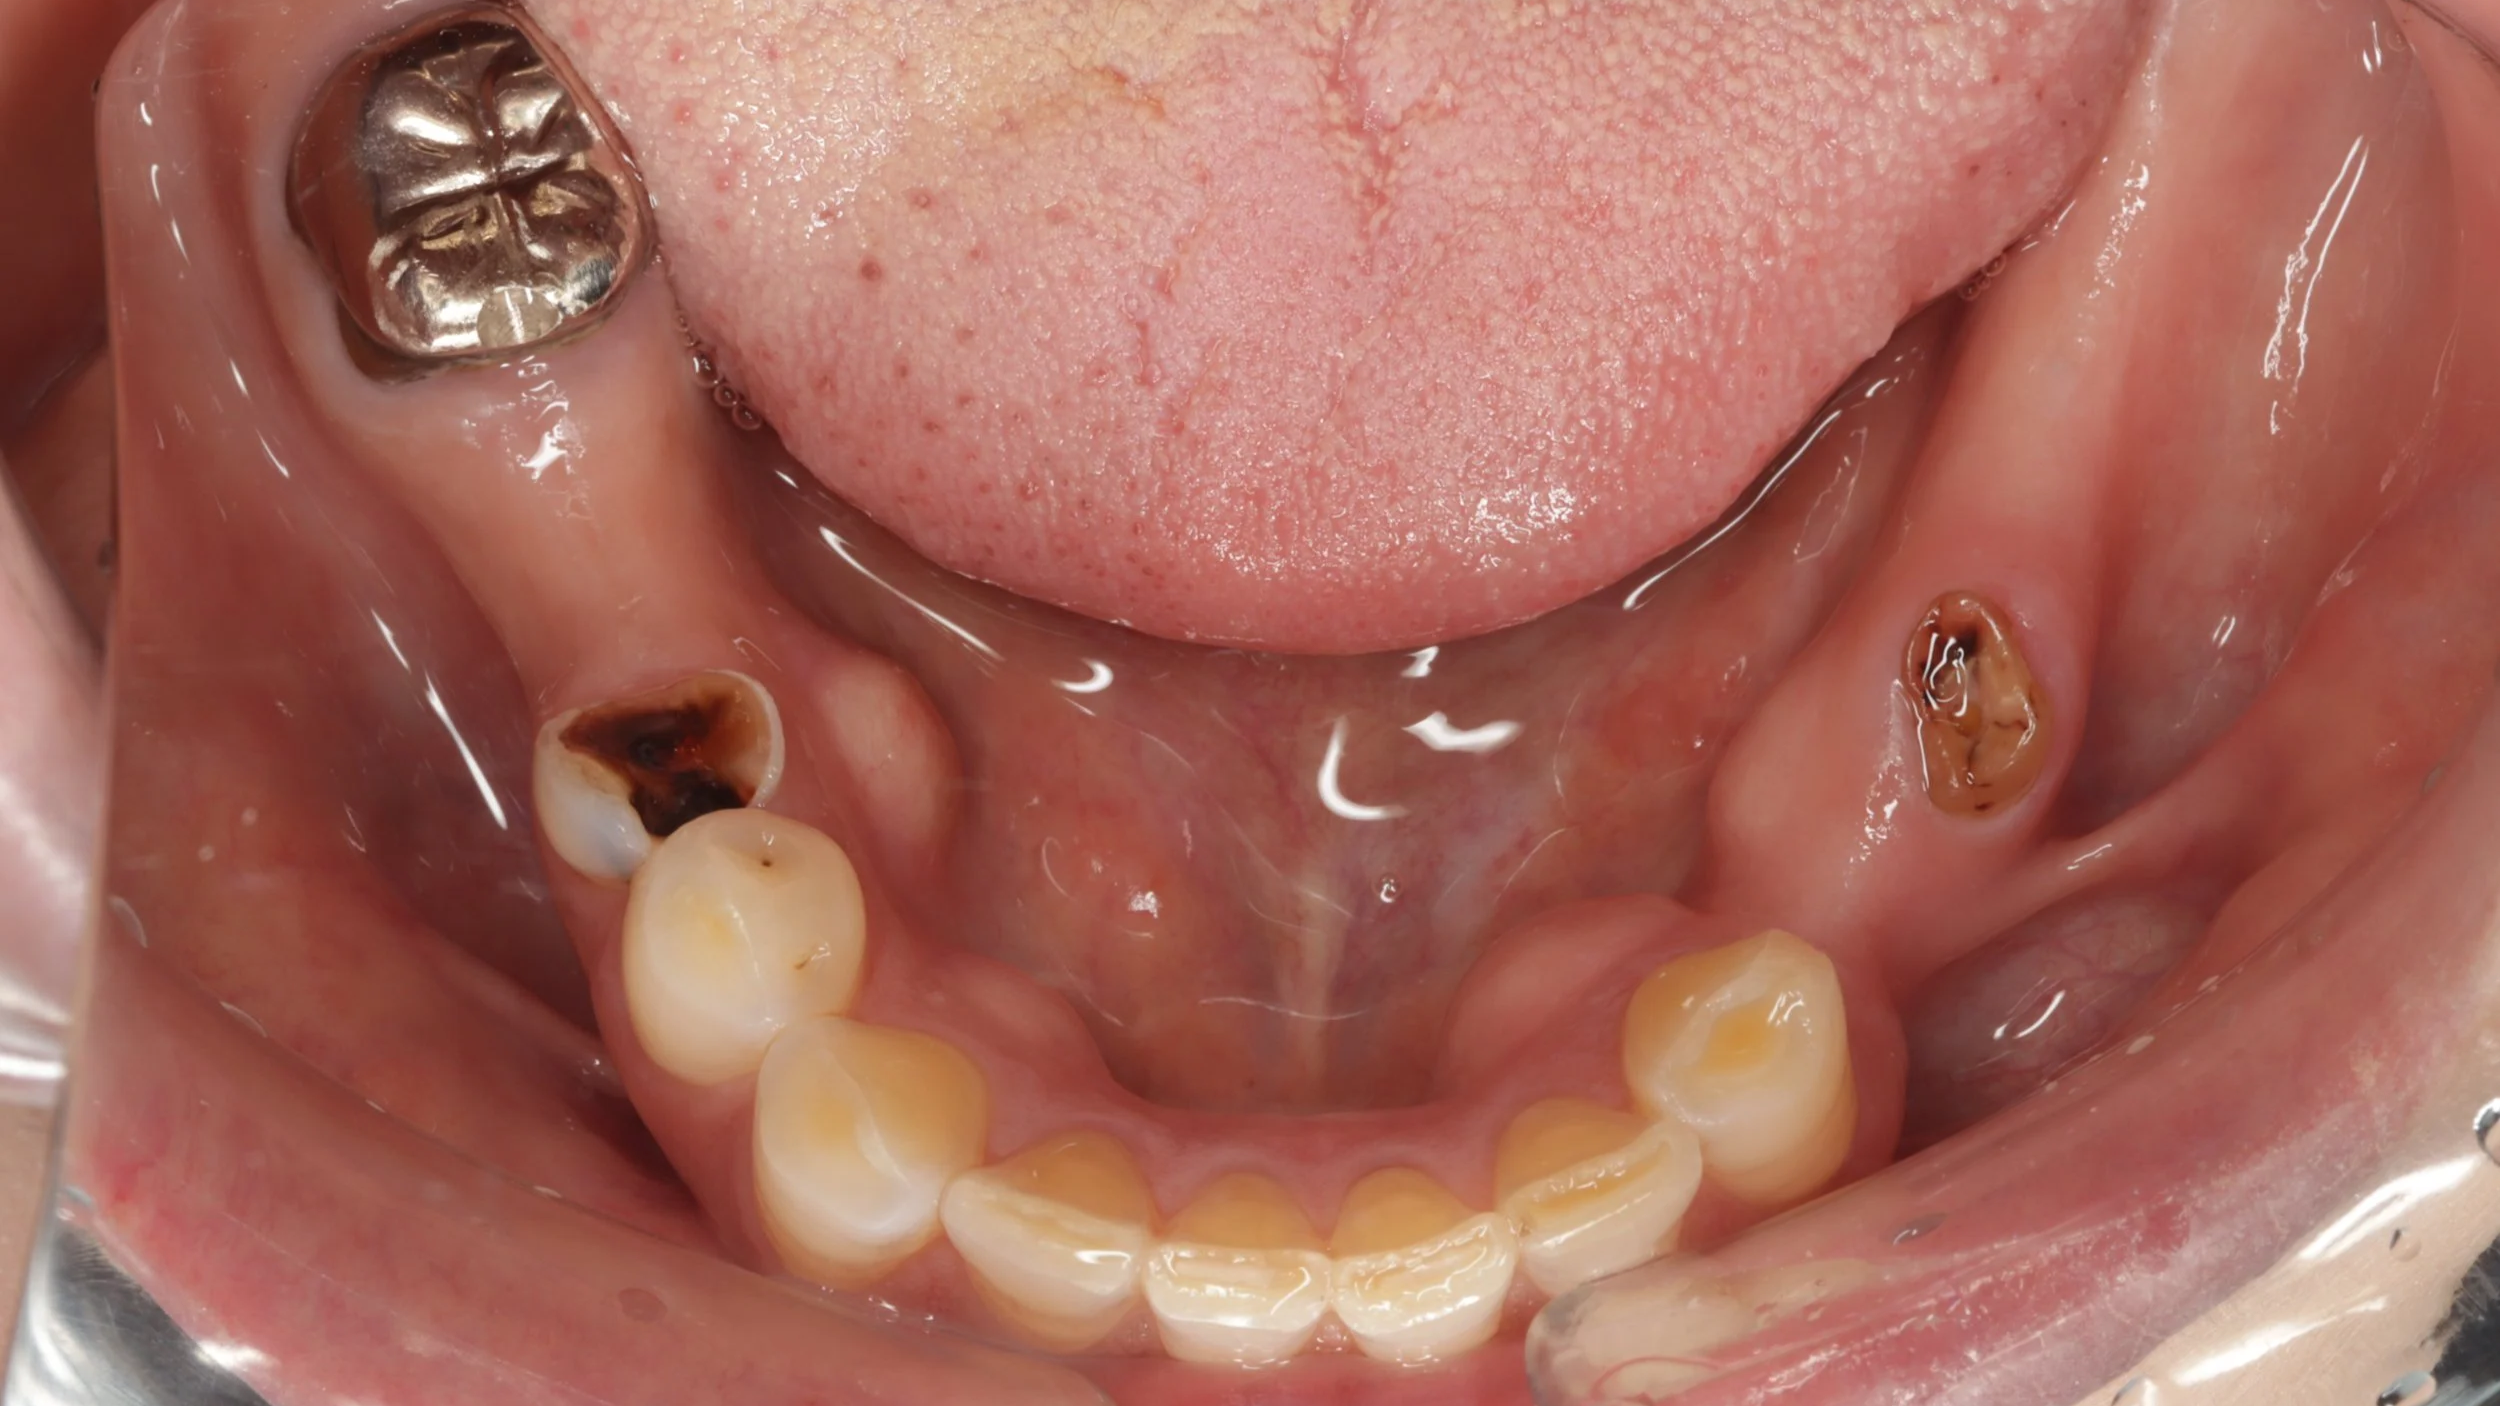

初診時

大きなむし歯もある状態でしたがまずは、入れ歯を早期に装着し、入れ歯の調整をしつつ、歯の治療することとしました。